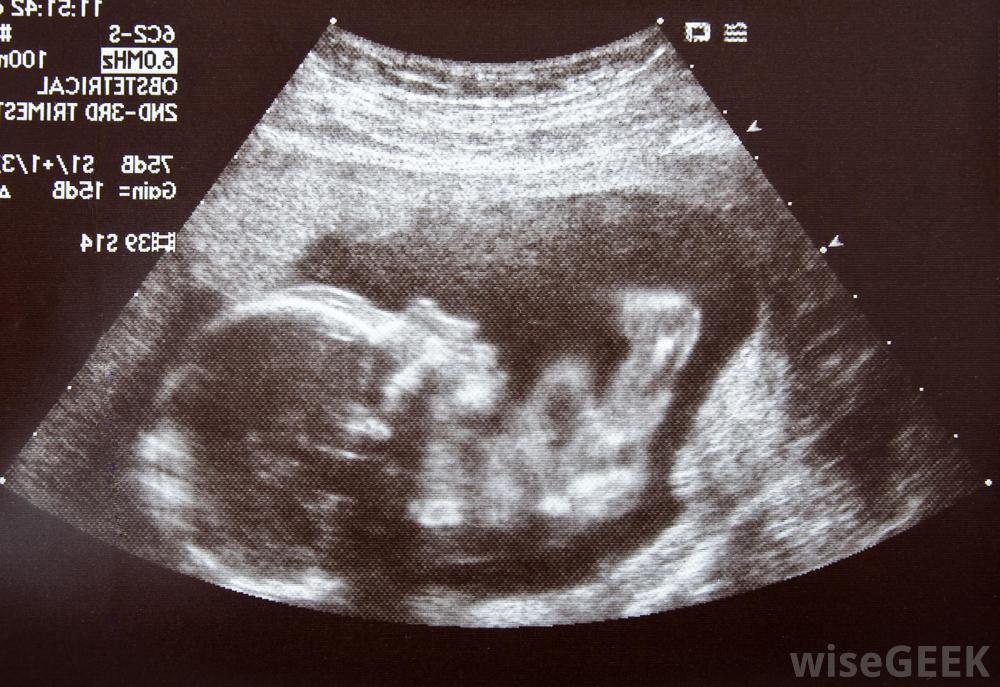

懷孕中期,胎兒發育突飛猛進。母親的妊娠癥狀也會發生一些變化。許多母親報告說,雖然個人經歷可能會有所不同,但中期妊娠是最容易懷孕的部分。流產的風險也從根本上降低了,而且是預期的當父母進入懷孕的這一階段時,他們通常會開始告訴朋友和家人。超聲圖像可以顯示中期胎兒的生長特征懷孕的第四個月、第五個月和第六個月,孕中期通常標志著疲勞、惡心、晨吐和乳房壓痛的消失。母親會注意到身體的變化,包括皮膚變黑、乳房腫脹和宮縮乏力的表現,稱為布拉克斯頓-希克斯宮縮。在懷孕的這個階段,一些陰道分泌物是正常的。當身體調整以給生長中的胎兒騰出空間時,女性可能會感到臀部和骨盆疼痛和酸痛婦女應在妊娠中期定期與醫生預約產前檢查,女性更容易發生尿路感染和膀胱感染,有些女性會出現便秘和痔瘡一些飲食調整可以讓女性感覺更舒服,并減少這些懷孕癥狀。女性通常也會在懷孕的這個階段開始表現出來,她們可能會注意到大腿和上臂等部位有體重增加的跡象孕婦必須在整個中期定期參加產前檢查,胎兒會形成一個睡眠-覺醒周期,變得更加活躍和好奇。在14到18周之間,胎兒會開始活動。妊娠中期發生的一些胎兒發育標志包括生殖器官的發育、吞咽反射的出現、毛發的生長,指紋的出現,骨骼的發育和聽力的發展。此外,胎兒能夠做出面部表情。懷孕中期既是胎兒快速生長的時期,也是許多婦女注意到晨吐癥狀消退的時期妊娠中期結束時,胎兒開始進入宮外生存狀態,緊急情況下必須分娩時,重癥監護可以讓它在母體外存活,早產對嬰兒來說有很多風險,如果可能的話,也會避免在妊娠中期,婦女應定期參加產前檢查,以便醫生、助產士或護士監督妊娠的進展情況。在此期間,也可提供產前檢查。婦女可以討論可用的檢查方法及其風險和益處。有些檢查很重要,因為他們可能會發現分娩和分娩過程中可能出現的問題。孕中期流產的風險大大降低。